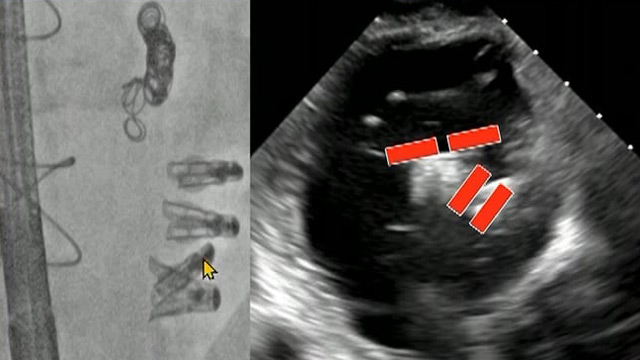

Mitral TEER masterclass

14 Feb 2026 – From PCR Tokyo Valves 2026

Delve into the mitral TEER masterclass focusing on unique anatomical challenges encountered in Asian populations. This session presents complex case studies illustrating device strategies and practical techniques aimed at minimizing complications and optimizing procedural outcomes in anatomically challenging scenarios.